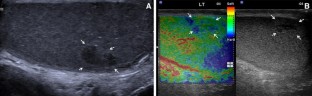

Fig. 4